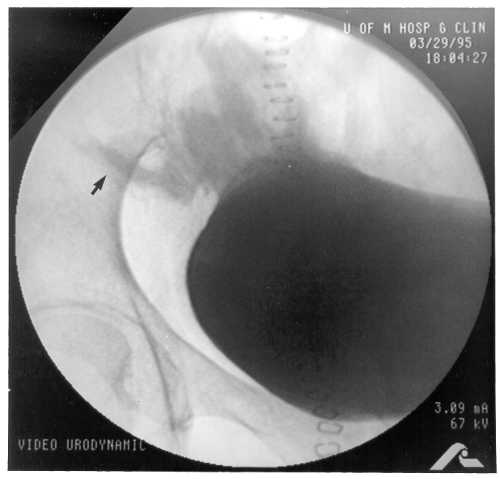

Case 1. A 38-year-old female underwent SPK. She lost kidney function due to an ischemic event (cortical necrosis by biopsy) and received a second kidney transplant (2 Dr match) 3 months later. Induction immunosuppression for the kidney included steroid bolus and recycling, and FK506 i.v. without antibody induction. She remained normoglycemic with normal serum and urine amylase. Six months later, after two kidney biopsy-proven acute rejection episodes, her creatinine was 1.4 mg/dl, but she was readmitted due to decreased urinary amylase (almost absent) and hyperglycemia for which she required insulin. US on admission demonstrated a dilated allograft pancreatic duct 10.3 mm (Figure 1). This improved with Foley catheter insertion. Video-urodynamics showed reflux into the pancreatic duct (Figure 2) and voiding in a not "relaxed manner" with evidence of pseudodyssynergia (Figure 3). Pancreas biopsy showed fibrosis without rejection. This patient requires insulin.

Figure 2. During the video-urodynamics, the patient was on supine position and monitored fluoroscopically. The bladder was filled with dilute contrast. Fluoroscopic control revealed a smooth walled bladder during the filling phase with a closed bladder neck. The patient experienced some reflux of urine into the duodenum segment and into the pancreatic duct during the height of the filling phase and especially during the voiding phase. |

Case 5. This case (a 41-year old male) is similar to case 4 with the only difference that the pancreatic duct measured 3.7 mm before the insertion of a Foley catheter. He was empirically treated for rejection (elevation of serum amylase/lipase and normal urine amylase) with improvement of the duct size (repeat US) after anti-rejection treatment. Six months after this event, he developed a recurrence. This time the US showed a duct size of 6.8 mm. A video-urodynamic study showed detrusor areflexia, he attempted to void by increasing abdominal pressure but no detrusor activity was noted with the voiding effort. The video phase of this study showed reflux into the duodenum at very low bladder pressures (<5 H2O). Although he was offered intermittent catheterization, he preferred and underwent conversion from bladder to enteric drainage successfully. This patient remains euglycemic, off insulin.